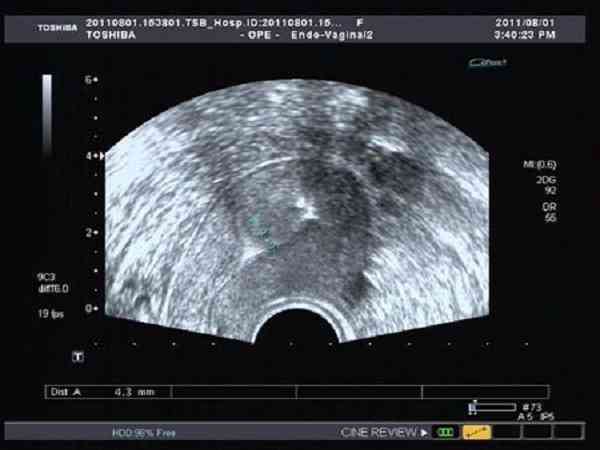

移植胚胎必须要憋尿,子宫前位看其宫腔得膀胱充盈

通常在进行试管移植时,医生基本上会要求每一位女性朋友憋尿,也就是说,不管是子宫前位还是后位,都是需要涨尿的,这样可以更方便医生看清图像,能更顺利的进行手术,减少仪器损伤子宫的概率,但是憋尿要注意适量,不可过多,也不可过少。胚胎移植需要少量多次喝水,让膀胱慢慢充盈,这种方法憋尿憋3至4小时,甚至4至5个小时不排尿,也不会感觉很尿急,并且也是很适合进行移植手术的,一般移植完再休息半小时左右就可以排尿了...